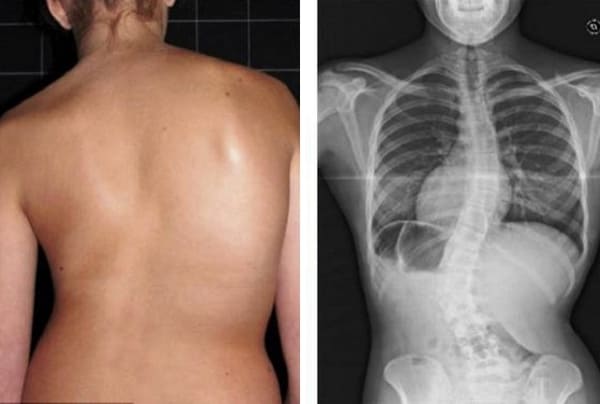

Todas as articulações requerem atenção, mas a coluna vertebral é prioritária. Preste atenção a ela antes que mudanças irreversíveis comecem a ocorrer. Eis o que espera àqueles que não prestaram atenção aos sinais do seu corpo: hérnia, deslocamento das vértebras, deformação da coluna vertebral, curvatura das costas, perda total da mobilidade. Não espere até que até mesmo um movimento simples se torne uma tortura!

Veja estas fotos. É isto que aconteceu com todos aqueles que ignoraram os sintomas. Hoje, estas pessoas estão completamente sem esperança e muitas delas não têm a quem recorrer para pedir ajuda. É mesmo isto que quer para a sua vida?

«Corcunda de viúva» — deformação da coluna vertebral e dor crónica e lancinante, que se intensifica a cada dia.

Hérnia do disco intervertebral, compressão do nervo, perda de sensibilidade e paralisia parcial das pernas.